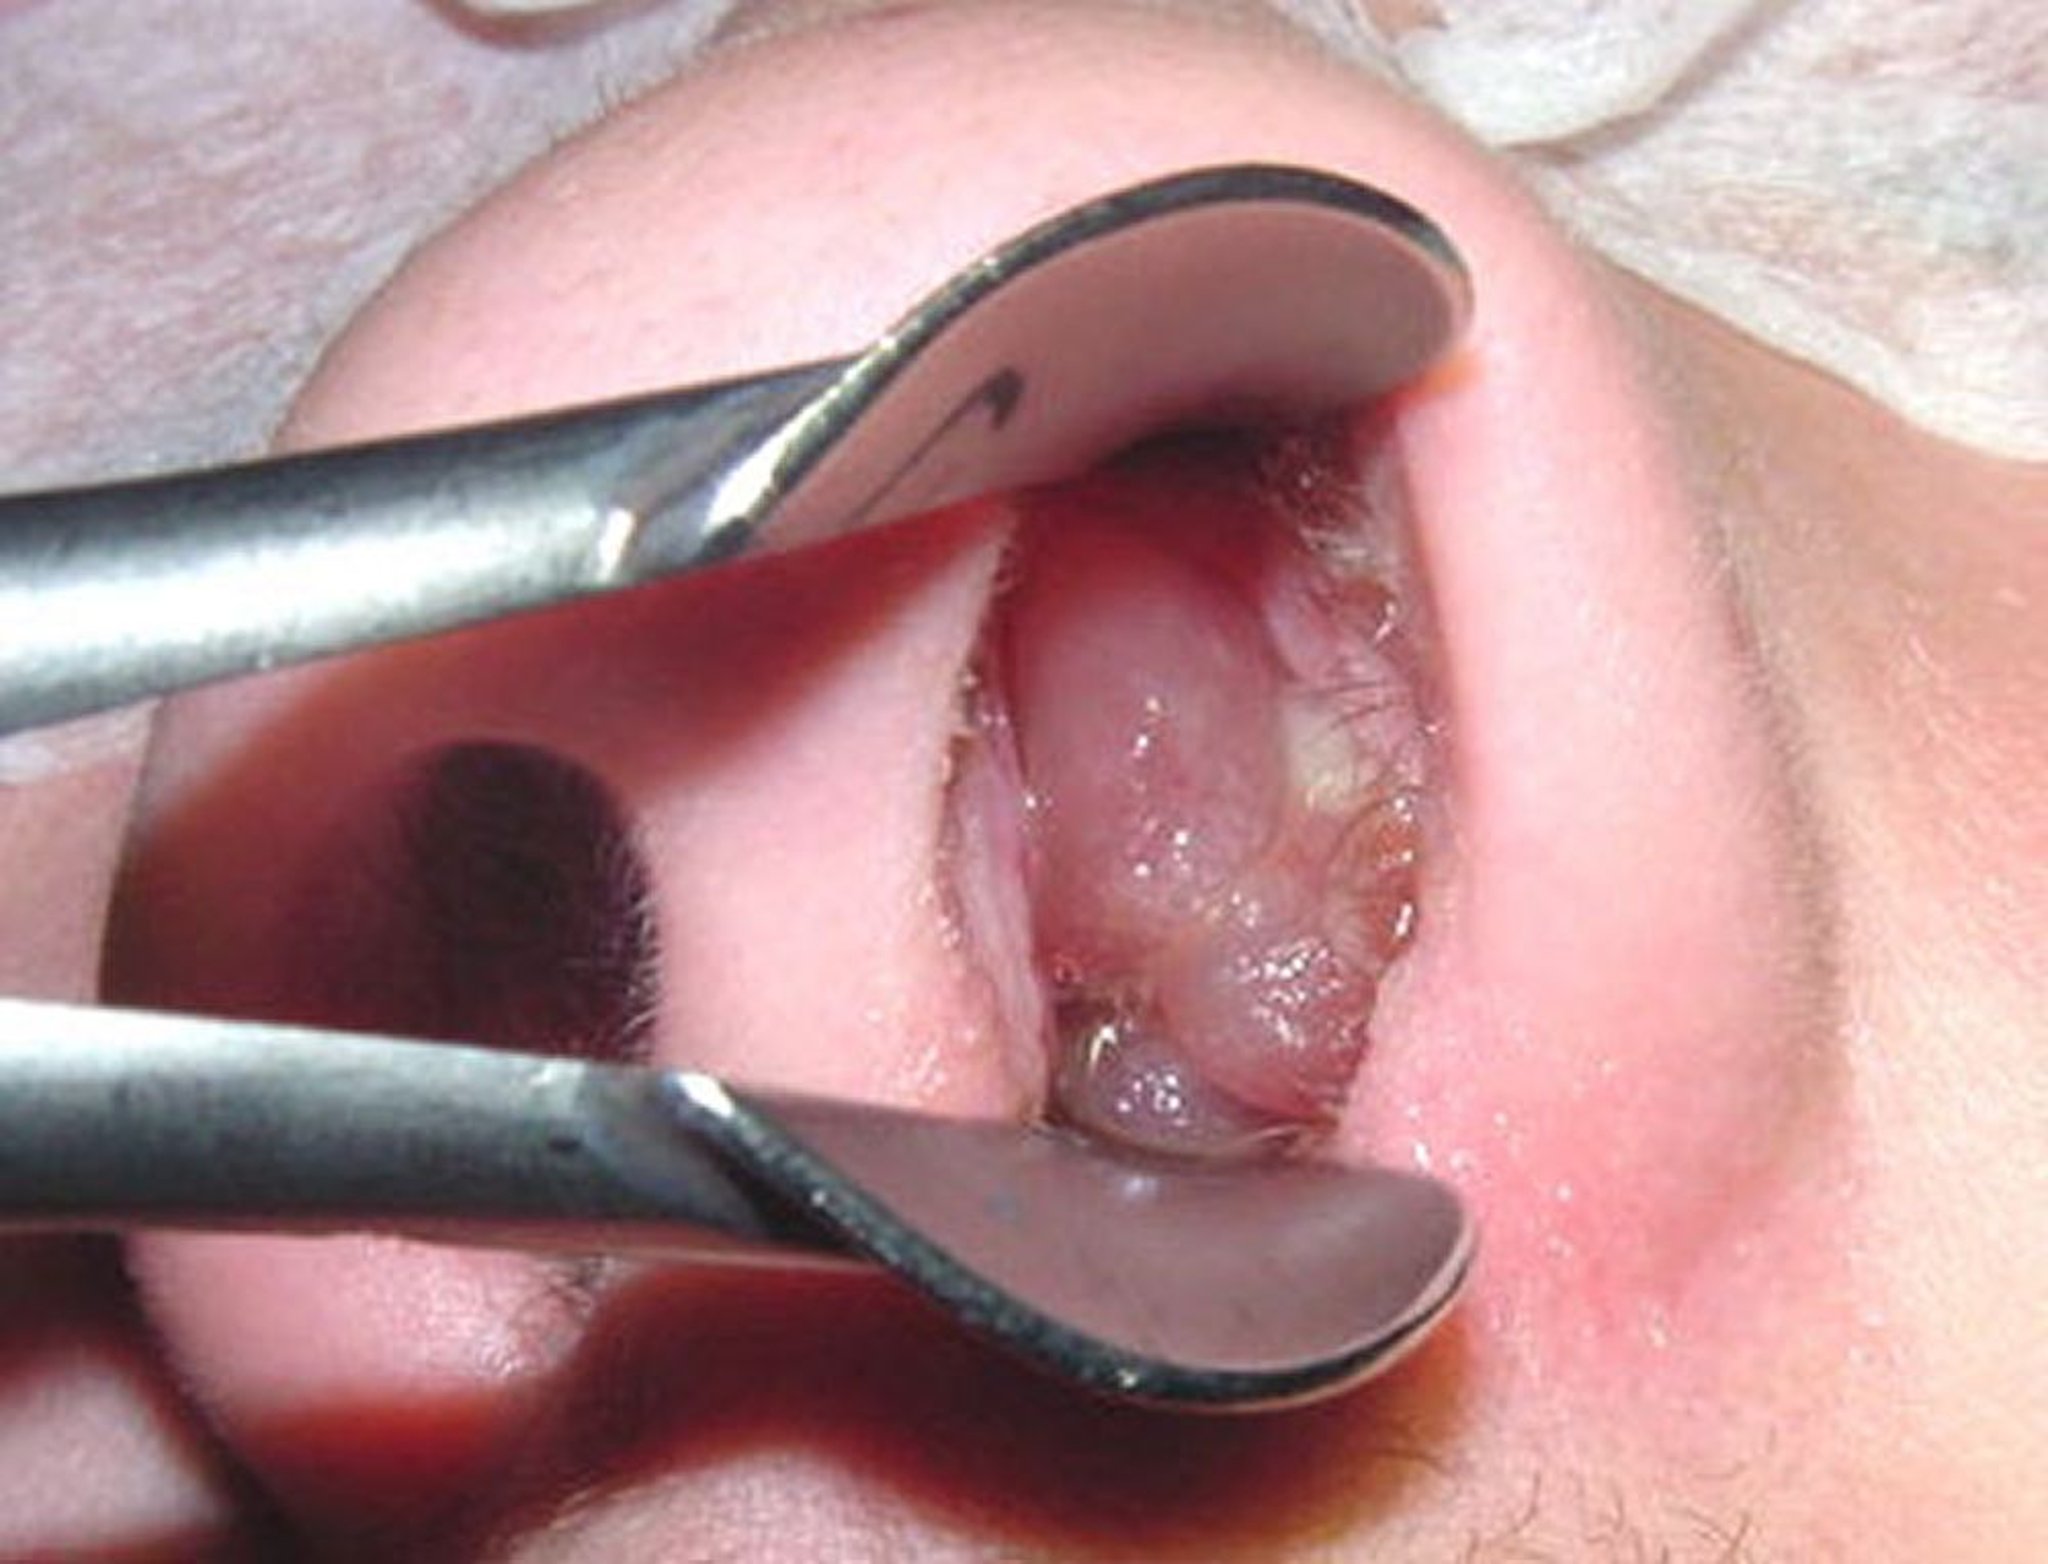

Ein reifer Polyp ähnelt einer geschälten, kernlosen Weinbeere.

Abbildung mit Genehmigung von Dr. med. Bechara Ghorayeb.